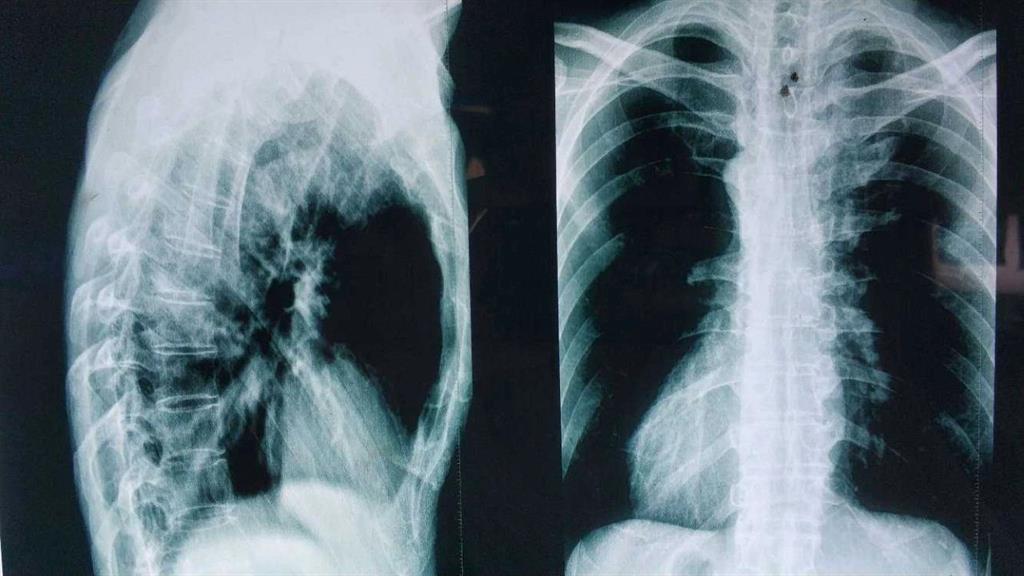

“HLA-B27陰性……從驗血報告來看是正常的……X光……也沒什么問題,這邊建議你再去拍個髖關(guān)節(jié)的核磁共振。”醫(yī)生轉(zhuǎn)過身對著男孩說。

“你這病本來就應(yīng)該到風濕免疫科來看,你之前去的骨科診斷會不一樣,現(xiàn)在這個片子看不到病痛的地方。”

看男孩不說話,醫(yī)生繼續(xù)說道:“你的HLA-B27顯示陰性,如果是陽性就可以確診是強直性脊柱炎,現(xiàn)在只能排查……如果確診是強直性脊柱炎,就要就要及早治療,因為這個病是不可逆的,我們只能延緩它病程進度……”